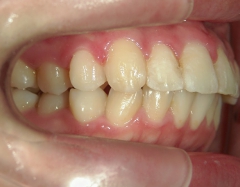

矯正歯科 治療前

no.6_8296_治療前_右.jpgno.6_8296_治療前_正面.jpgno.6_8296_治療前_左.jpg